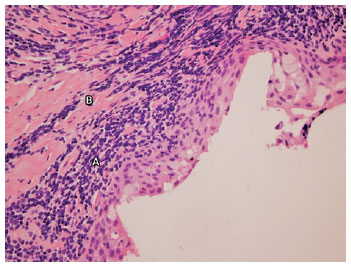

Oral antibiotics were administered, along with topical steroids and lubrication with artificial tears and ointments. After 1 week of treatment, no changes were observed in the clinical appearance of the eyelids; furthermore, the conjunctiva continued to exhibit thickening and a reddened appearance. Magnetic resonance imaging ruled out orbital mass or malignancy, and indicated inflammatory disease involving the conjunctiva. Oral prednisone 0.5 mg/kg/day was initiated. A conjunctival biopsy was obtained from the inferior eyelid and serologic testing was performed for anti-basement membrane zone antibodies and anti-intercellular substance antibodies, due to initial suspicion of MMP. Histopathological examination revealed epithelium with inflammatory changes, as well as submucous lymphocytes with band-like distribution and foci of exocytosis. Based on these findings, a diagnosis of LP was suggested (Figure 2). Direct immunofluorescence examination revealed shaggy distribution of fibrinogen; moreover, anti-basement membrane zone antibodies and anti-intercellular substance antibodies were absent from the serum. A thorough general examination was performed, and no other skin or mucosal lesions were found. After diagnosis, treatment was adjusted, including tapering of oral steroids; topical cyclosporin 2% was initiated. Due to poor tolerance, treatment was modified; stabilization of symblepharon was achieved without any further eyelid malposition, as well as remission of the conjunctival hyperemia and symptoms, by using preservative-free topical dexamethasone t.i.d. and topical cyclosporine 1% b.i.d (Figure 3). No improvement in the graft was observed and visual acuity remained light perception.

Pathological findings have been defined previously. In patients with oral-mucosal LP, lymphocytes (specifically T-helper cells and cytotoxic T cells) infiltrate the basement membrane zone, accompanied by Langerhans cells and macrophages(2). Similar findings have been described in biopsies of the conjunctiva in patients with ocular LP(5,6). The presence of a coarse, shaggy distribution of fibrinogen at the basement membrane zone, detected by direct immunofluorescence, may also be helpful(5,7).